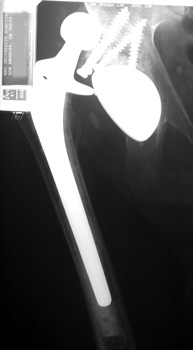

Dislocated femoral component secondary to steep acetabular cup inclination, pre and post revision. Note constraining ring about femoral head, which helps maintain head in cup